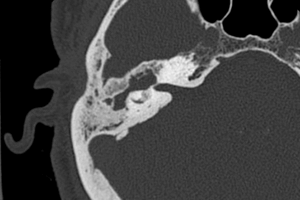

Labyrinthitis Ossificans

What anatomic structure of the middle or inner ear is abnormal in this patient with hearing loss and a history of childhood meningitis? Read more »